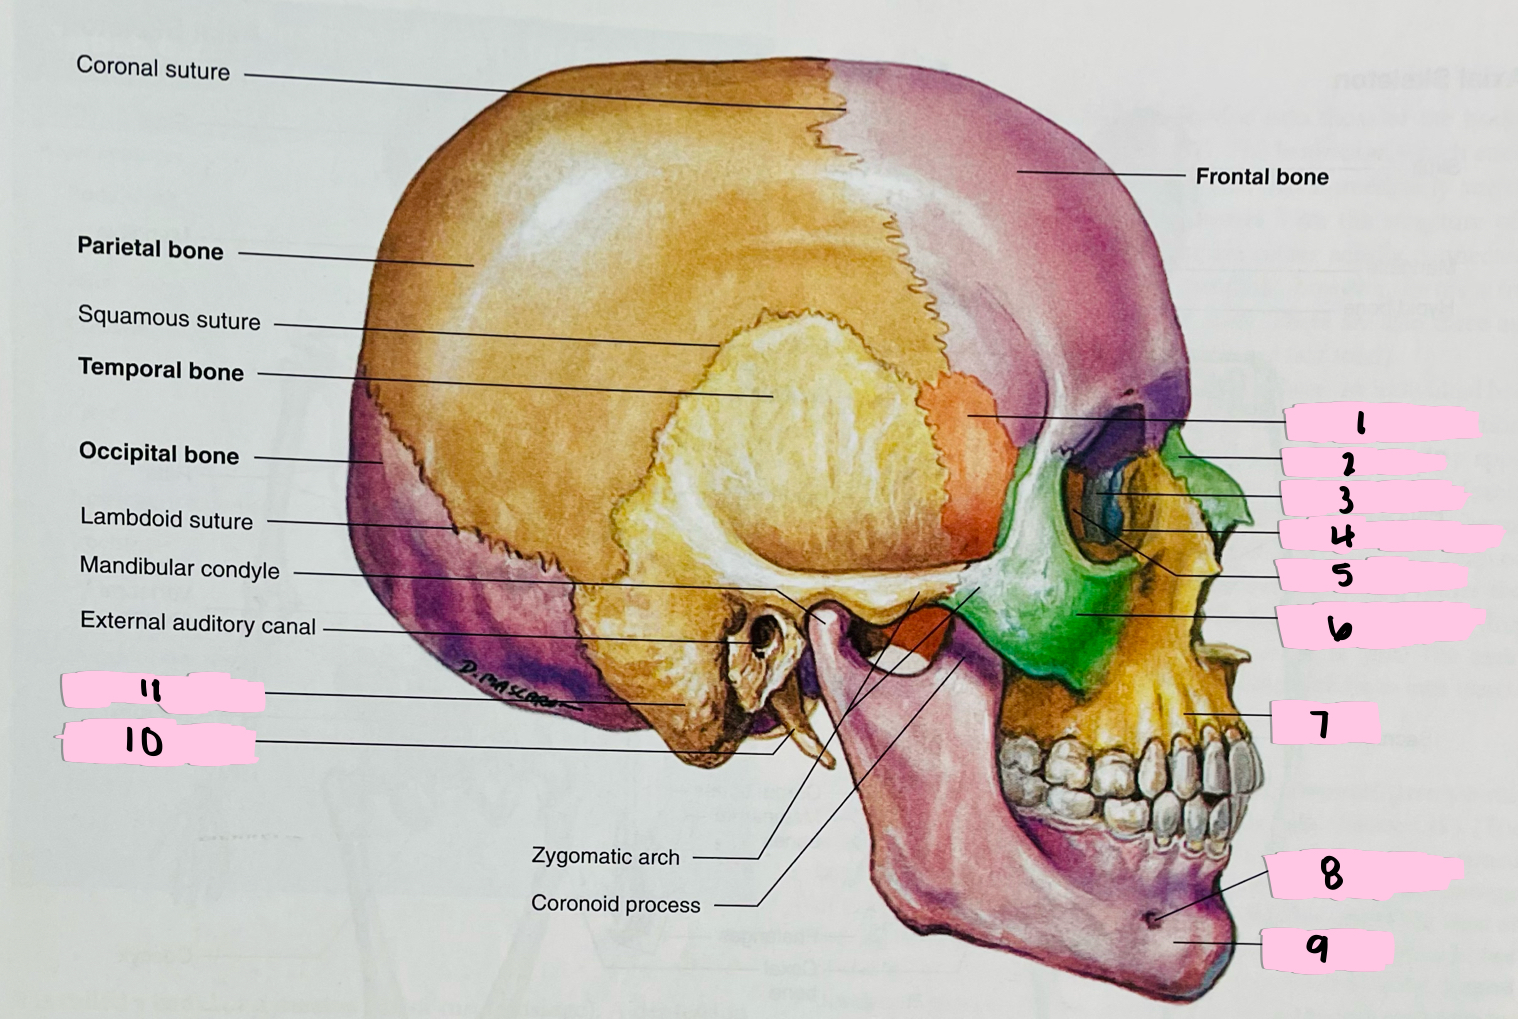

What is 1 pointing to?

Sphenoid bone

What is 2 pointing to?

Nasal bone

What is 3 pointing to?

Lacrimal bone

What is 4 pointing to?

Nasolacrimal canal

What is 5 pointing to?

Ethmoid bone

What is 6 pointing to?

Zygomatic bone

What is 7 pointing to?

Maxilla

What is 8 pointing to?

Mental foramen

What is 9 pointing to?

Mandible

What is 10 pointing to?

Styloid process

What is 11 pointing to?

Mastoid process